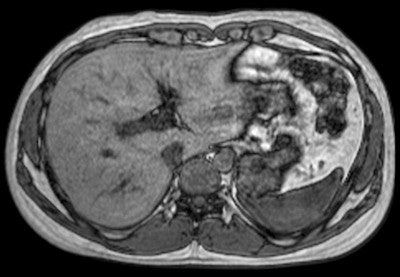

Expanding on its global R&D footprint that includes a new high-tech facility in Suzhou, China, Philips has developed a reliable and simple to use machine for developing markets. The Multiva 1.5-tesla unit is designed to ease patient discomfort and increase productivity by reducing the time spent setting up an examination. It features the FlexStream workflow system, which enables efficient handling of coils for head, spine, musculoskeletal, and neurovascular examinations, allowing a reduction of up to 40% in the time it takes to position the patient and coils before securing an image, according to the manufacturer.

Another feature of the Multiva system is SmartSelect software, which automatically determines which coils and elements should be activated to yield the maximum SNR in the region of interest for greater efficiency and higher image resolution. Additionally, a large neurovascular coil design allows patients to use headphones during their examination, which can help improve patient comfort. These improvements will maximize the value of the system and allow clinicians to treat more patients each day without compromising image quality, the company explained.